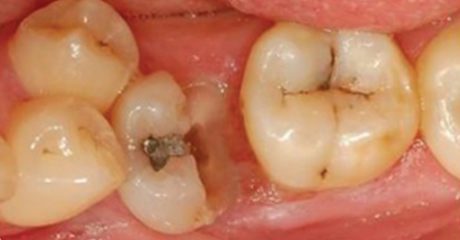

치아가 녹아버리거나 부러져버리는 상황에 이르게 됩니다.

신경제거 후 신경으로부터 받던 영양분을 공급받지 못해 약해진 치아는 작은 충격에도 금이 가거나, 부러지거나, 깨져버리기 때문에 단단한 크라운을 씌워 치아를 보호해야 합니다.

신경치료를 위해 치아가 아래ㆍ위 치아가 닿지 않게 조절을 하며 치아에 구멍을 뚫어 놓기 때문에

씌워야 기능을 수복할 수 있습니다.